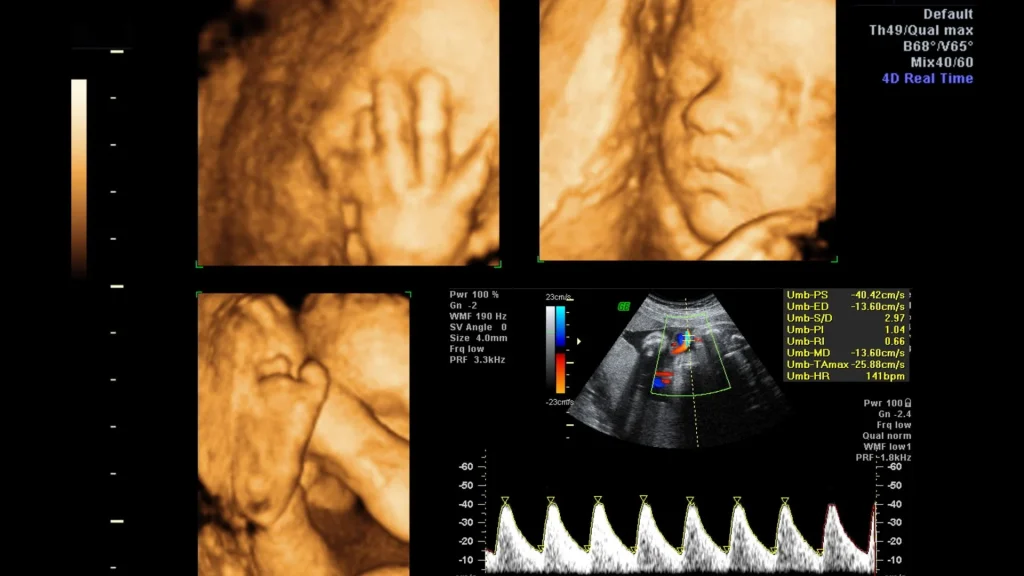

USG dengan AI Auto Measurement memungkinkan dokter melihat jantung janin secara real-time dengan detail tinggi. Citra ini memperlihatkan struktur bilik, katup, dan pembuluh darah secara jelas, memudahkan evaluasi anatomi kompleks. Deteksi kelainan jantung sejak dini menjadi lebih akurat dan cepat.

Fitur AI melakukan penghitungan dimensi bilik, volume jantung, dan aliran darah secara otomatis. Proses ini mengurangi ketergantungan pada keterampilan operator dan meningkatkan konsistensi hasil. Akurasi tinggi membantu dokter menilai pertumbuhan jantung janin dengan lebih tepat.

AI memungkinkan evaluasi fungsi jantung janin, termasuk kontraksi bilik, aliran darah, dan efisiensi pompa jantung secara real-time. Data ini mempermudah penilaian kesehatan jantung dan deteksi perubahan sejak dini. Pemantauan berkelanjutan mendukung intervensi tepat waktu.